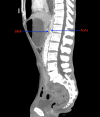

Cast syndrome, commonly known as superior mesenteric artery (SMA) syndrome is a rare cause of small bowel obstruction caused by compression of third part of duodenum from narrowing of the angle between superior mesenteric artery and abdominal aorta resulting in symptoms of duodenal outflow obstruction. A 46-year-old male presented with acute worsening of chronic abdominal pain, nausea and vomiting aggravated with eating. Computed tomography of abdomen and pelvis revealed the dilatation of gastric and proximal duodenum due to compression of third part of duodenum between superior mesenteric artery and aorta. Conservative management with total parental nutrition failed and patient underwent gastrojejunostomy with relief of his symptoms. Cast syndrome is a rare condition but should be kept in mind in patients with abdominal pain, vomiting, early satiety and weight loss. CT abdomen usually reveals the diagnosis but upper GI endoscopy helps to rule out other causes of duodenal obstruction and gastric dilatation.